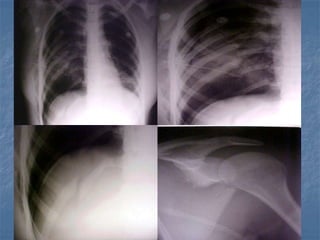

11. Fractura escapular

12. Luxación escapulotorácica

13. Fractura de clavícula

14. Luxación esternoclavicular

15. Fractura de esternón

16. Fractura de 1a. Y 2a. Costillas

17. Fracturas costales